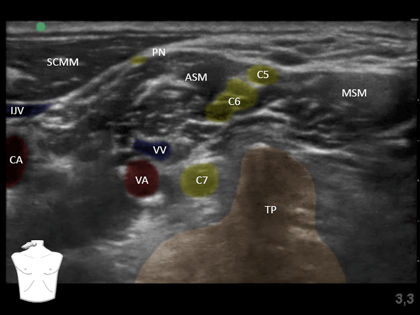

Interscalene Block

A

Supine, head turned contralateral

Depth 1 - 4 cm

22 G 50 mm needle

10 mL 0.2% for analgesia, 15 -20 mL 0.5% for anaesthesia

Ulnar sparing